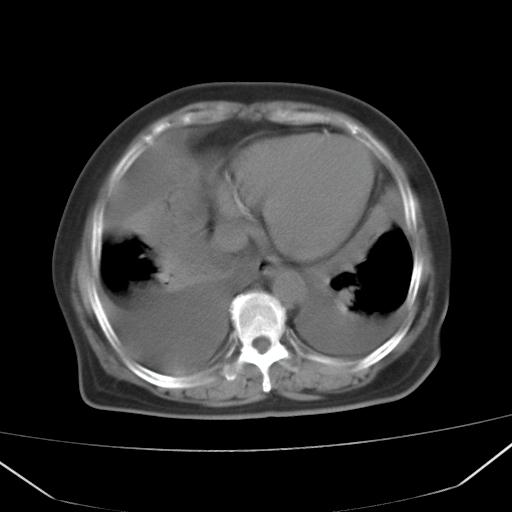

以下是引用liuyue在2008-4-19 22:25:00的发言:[br]先考虑:1.心衰伴肺水肿、双侧胸腔积液、叶间积液、双下肺不完全性肺不张; [br] 2.冠状动脉粥样硬化。

以下是引用lijuanln在2008-4-19 23:05:00的发言:[br]两侧胸腔积液,肺水肿[br]心包积液[br]提示心衰

以下是引用jiangjing在2008-4-20 10:43:00的发言:[br]结合病史支持 冠心病[冠状动脉钙化],心功能不全,肺淤血、肺水肿,双侧胸腔与斜裂积液